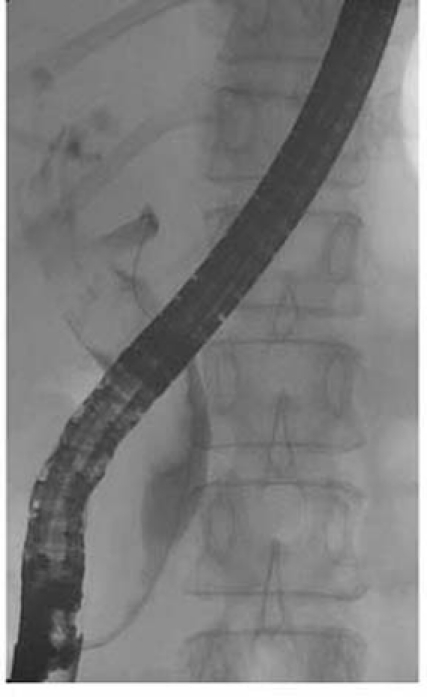

This patient was immediately sent for imaging studies. The ‘B’-ultrasound showed a swollen gallbladder measuring 146 × 40 mm2 with a wall thickness of 2 mm. Within the gallbladder, there were many gallstones together with a space-occupying mass, which showed irregular and uneven echogenicity. The largest gallstone was 14 × 9 mm2 in size. The gallbladder mass did not move along with patient’s posture change (figure 1). The inner diameter of the common bile duct was 22 mm. It was filled up with punctuated isotropic echoing substances. The intrahepatic ducts showed widespread dilation, measuring 5–7 mm in diameter. The abdomen CT with contrast showed gallbladder mass intermingled with gallbladder stones, enlarged hilar lymph nodes, dilated intrahepatic ducts and multiple liver cysts (figure 2). However, chest CT and pelvis CT did not show any additional mass lesion. Then, an endoscopic retrograde cholangiopancreatography was performed, which showed that the common bile duct was 20 mm in diameter. Within it, there was a 15 × 5 mm2 filling defect extending from hepatic hilum to the middle of common bile duct. The intrahepatic ducts were dilated and the gallbladder was partially shown. The inserted T-tube drained out blood-stained bile (figure 3).

Figure 3.

ERCP exam.